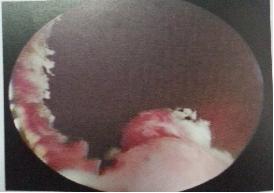

经皮肾镜手术技术:需要在超声或X射线定位引导下,经过腰背部皮肤穿刺到达肾盂,再经此通道放入肾镜,进行肾脏和部分上端输尿管疾病的诊断和治疗的微创手术技术。可应用于经皮肾镜检查、经皮肾镜碎石取石术、经皮肾盂输尿管连接处狭窄切开术、经皮肾镜异物取出术、经皮肾盂肾盏肿瘤治疗等。其中经皮肾镜碎石取石术为临床上最为常用的经皮肾镜手术技术。通过腰部小通道,可达到良好的肾结石清石效果。

1)取截石位,经尿道患侧输尿管置入输尿管导管至肾盂并固定。2)留置导尿,开放尿袋。

2)取俯卧位,B超引导下穿刺、扩张,建立经皮肾通道。

3)置入输尿管肾镜,直视下激光击碎结石,并冲出。

4)检查各个肾盏,防止结石残留。

5)经输尿管镜输尿管内置入双J管一根。

7)留置肾造瘘管并固定。